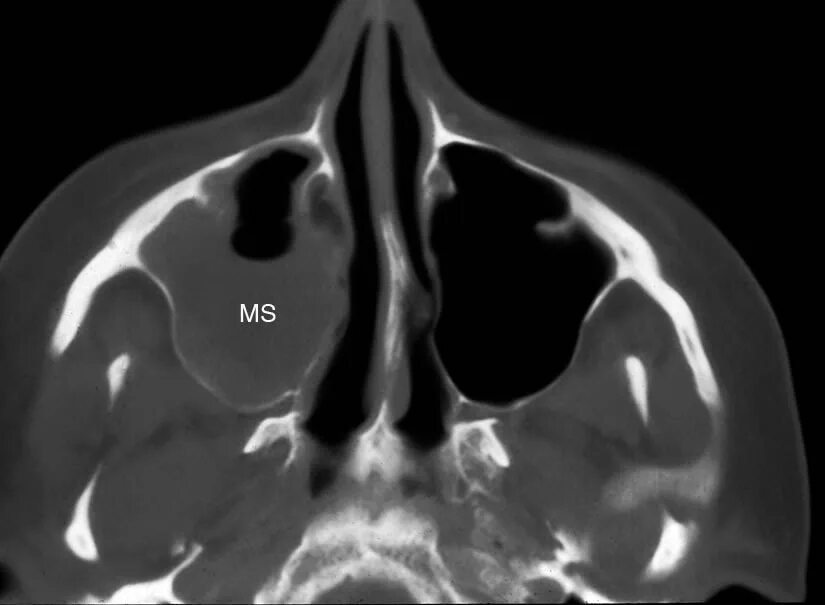

Как лечить утолщение слизистой верхнечелюстной пазухи